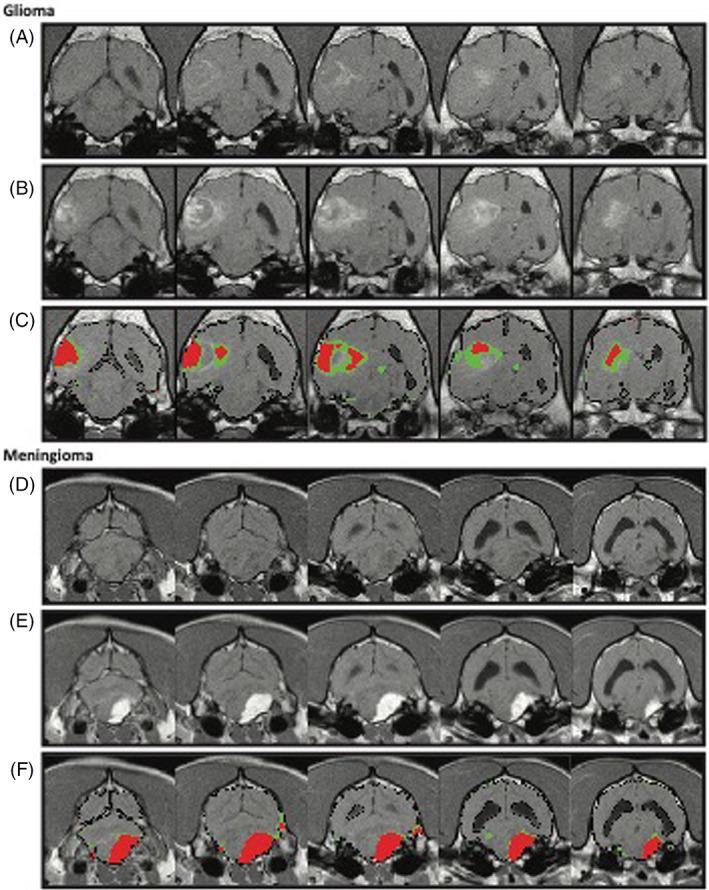

In a 2-arm study, images from a prospective dynamic contrast-enhanced (DCE; n = 15) and a retrospective archived magnetic resonance imaging study (n = 63) were analyzed by DCE and subtraction enhancement analysis (SEA) to quantify BBB permeability in affected dogs relative to control dogs (n = 6 in each arm). For the SEA method, 2 ranges of postcontrast intensity differences, that is, high (HR) and low (LR), were evaluated as possible representations of 2 classes of BBB leakage. BBB score was calculated for each dog and was associated with clinical characteristics and tumor location and class. Permeability maps were generated, using the slope values (DCE) or intensity difference (SEA) of each voxel, and analyzed.

Distinctive patterns and distributions of BBBD were identified for intra- and extra-axial tumors. At a cutoff of 0.1, LR/HR BBB score ratio yielded a sensitivity of 80% and specificity of 100% in differentiating gliomas from meningiomas.

在一项 2 臂研究中,对前瞻性动态对比增强(DCE;n=15)和回顾性存档磁共振成像研究(n=63)的图像进行了分析,通过 DCE 和减去增强分析(SEA)来定量受影响犬相对于对照犬(每臂 6 只)的 BBB 通透性。对于 SEA 方法,评估了 2 个范围的对比后强度差异,即高(HR)和低(LR),作为 2 种 BBB 渗漏的可能代表。为每只狗计算了 BBB 评分,并与临床特征、肿瘤位置和类型相关联。使用每个体素的斜率值(DCE)或强度差异(SEA)生成了渗透率图,并进行了分析。

确定了颅内和颅外肿瘤的独特的 BBBD 模式和分布。在 0.1 的截止值下,LR/HR BBB 评分比在区分神经胶质瘤和脑膜瘤方面具有 80%的敏感性和 100%的特异性。